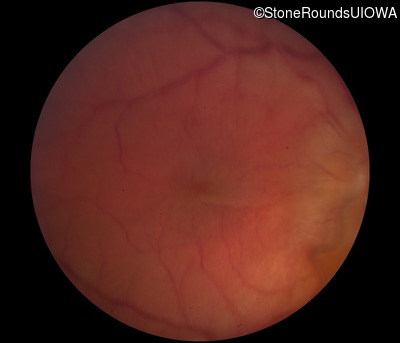

Fundus Photography - Right - 20/50 -1 sc

Exemplar